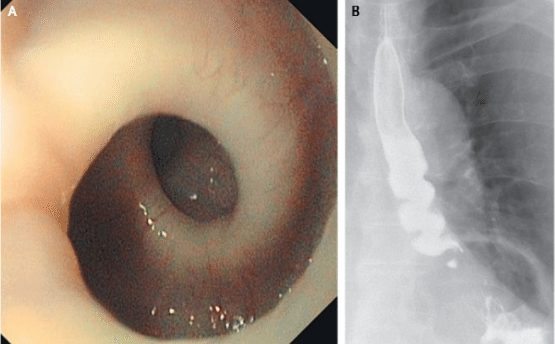

13 – Esôfago torcido

Uma senhora de 87 anos, na Suíça, procurou ajuda médica quando passou a experimentar espasmos dolorosos toda vez que engolia um alimento. Por meio de radiografias, os médicos descobriram que o esôfago da paciente se torcia como um saca-rolhas todas as vezes que tentava comer. A condição fez com que ela perdesse cerca de cinco quilos ao longo de alguns meses, de acordo com o relatório do caso, publicado em maio deste ano no New England Journal of Medicine.

Embora a condição seja estranha, ela não é completamente desconhecida pela Medicina. Acredita-se que espasmos musculares sejam os culpados para esse tipo de dor. Logo, ao invés de se contrair e relaxar, os músculos do esôfago da paciente simultaneamente se contraem. Não há curas disponíveis para a condição.